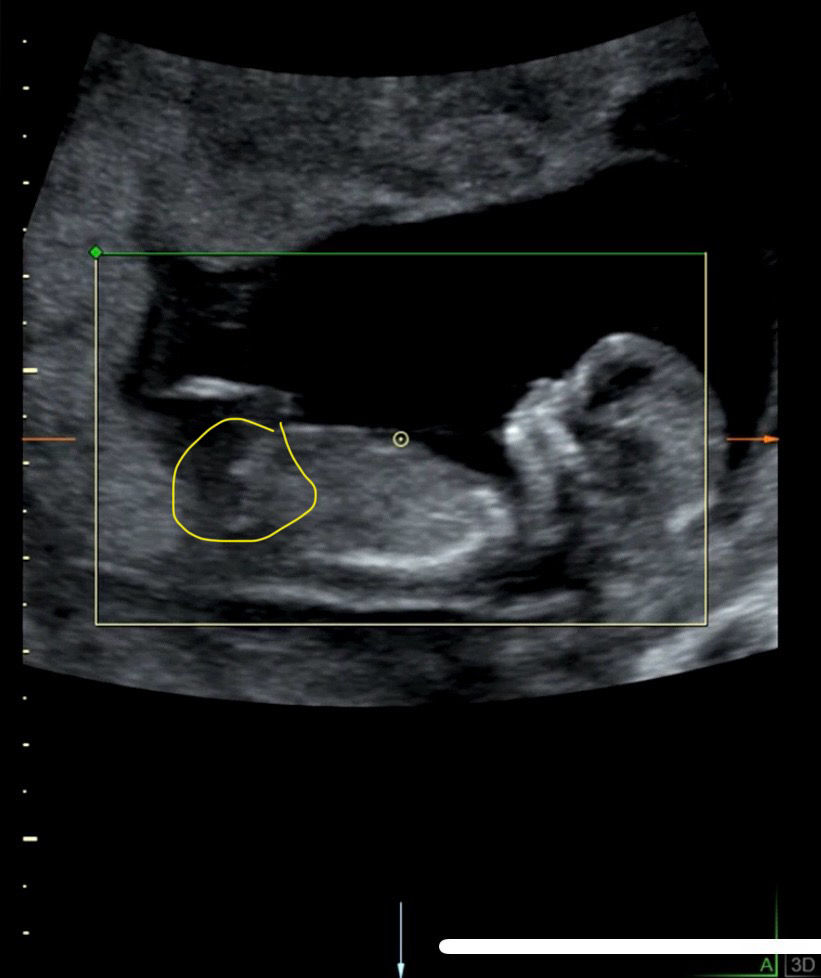

각도법 문의드려요 12주0일

도저히 생식기같은게 보이질 않아서 ㅠㅠ 저 노랗게 동그라미친 부분이 생식기가 맞을까요?..

생식기 돌기가 맞다면 딸 각도 같이 보이네요.

딸같아요